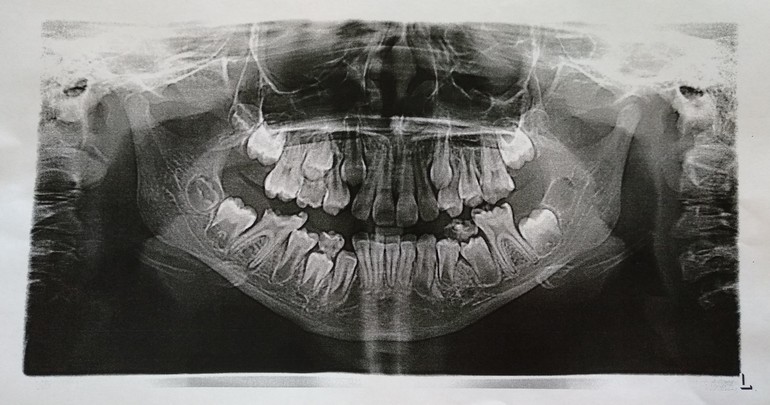

Удалять ли постоянный 6 зуб ???

Всем добрый день. Назрел вопрос о сохранении 6 зуба справа. Но так как он очень запущен, поэтому решила уточнить ваши мнения. Запущен т.к. страх, паника врачей и лечения. Началось с болей, потом припухла щека, поехали клинику святого Владимира, госпитализировали с диагнозом серозный периостит, лимфаденит. Врач хирург говорит сначала лечим все это и смотрим удалять или сохранять. Вра

ч стоматолог говорит удалять зуб, т.к. нет гарантии что даст должным образом полечить и чтобы дальше все пошло и не стало ещё хуже. Интересно ваше мнение.